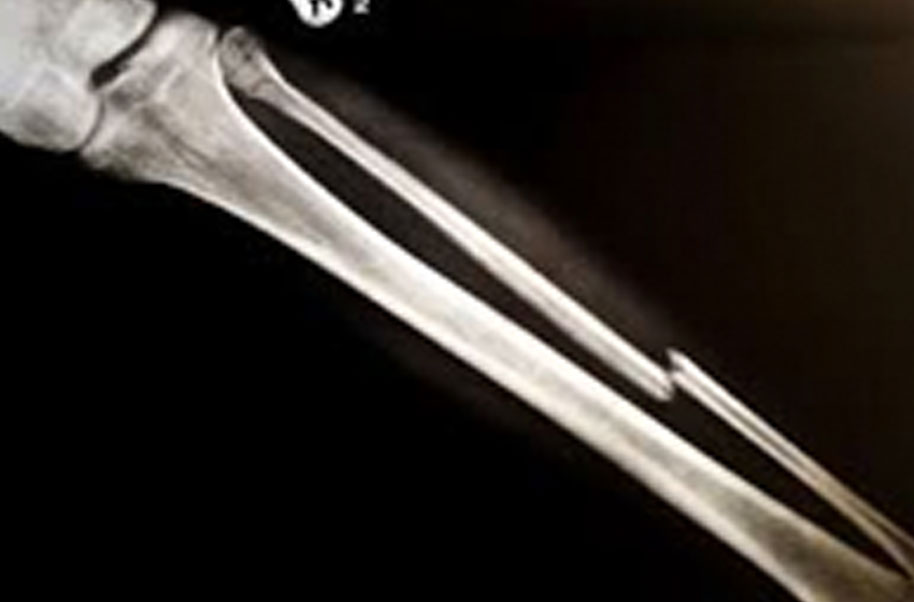

Hyoid (Broken Bone)

A complete or partial break in a bone.

- Treatment often involves resetting the bone in place and immobilising it in a cast or splint to give it time to heal. Sometimes, surgery with rods, plates and screws may be required.

Causes of bone fractures include trauma, overuse and diseases that weaken bones.